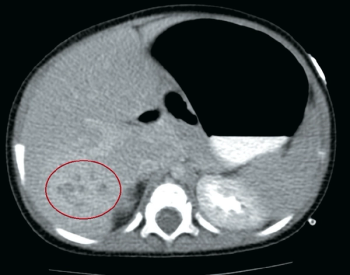

A 6-day-old, late-preterm male neonate presents to his pediatrician’s office with bilious emesis and is admitted for further evaluation. He was born at 36 weeks and 6 days via spontaneous vaginal delivery to a 23-year-old G4P4 mother with negative serologies, negative antenatal Group B Streptococcus testing, and no significant prenatal events. His stay in the newborn nursery was unremarkable. The neonate is exclusively breastfed, has no history of rectal bleeding, and passed meconium within the first 24 hours.